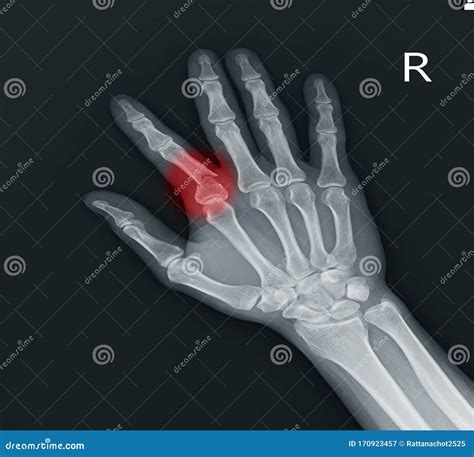

Diagnosing a Proximal Phalanx Broken

If you suspect a proximal phalanx broken, it is crucial to seek medical attention immediately. The diagnosis typically involves a physical examination and imaging tests. The most common diagnostic tools include:

• X-rays: To visualize the fracture and determine its severity.